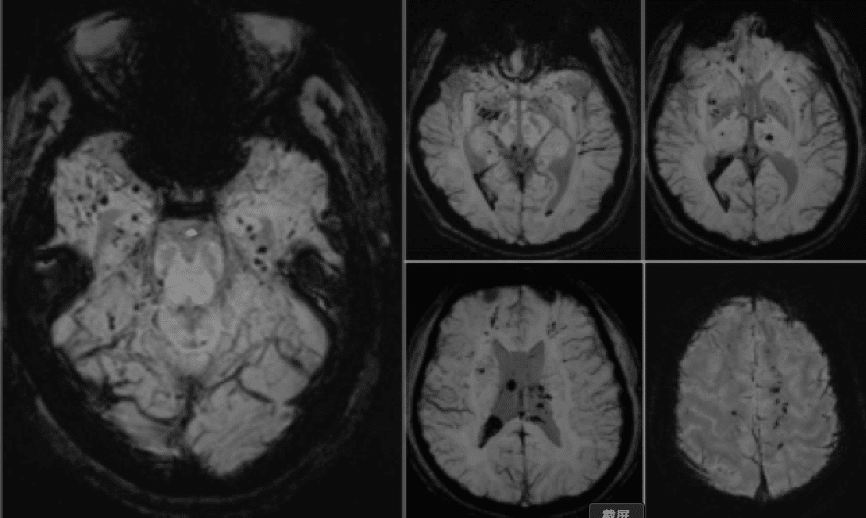

SWI(2014-12-30):双侧小脑、大脑实质内及右侧侧脑室后角可见多发点状、片状低信号。